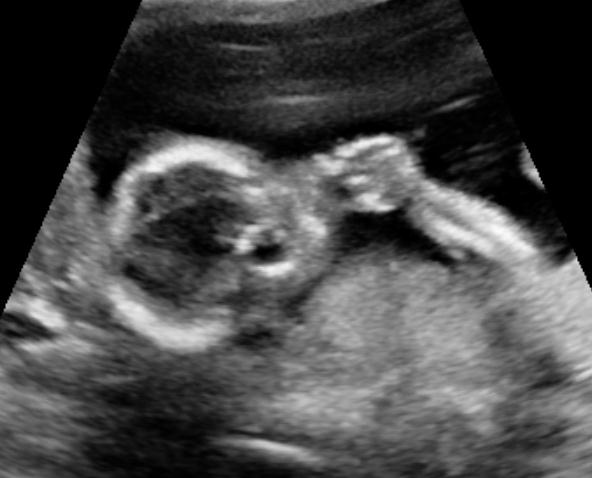

10 weeks: We first "saw" him on an ultrasound! He was really more a blob with a flashing light for a heartbeat. Keith was excited to be called "Dad" by the tech!

16 weeks: We got to see him again since he was moving too much to get an accurate heartbeat read with the dopplar. Keith got to be there with me for that appointment too, which is where we saw an actual baby-shaped object on the screen with kicking legs! I love that Keith is just as excited as I am and asked if I could feel his little kicks. I couldn't at the time, but it was coming!

28 weeks: Where I'm at now. Boy Gilbert is now 2.5 times bigger than he was in the U/S pic, and boy do I feel it! He must be a little cramped too, which is why he's stretching, rolling, and jabbing at miscellaneous internal organs.